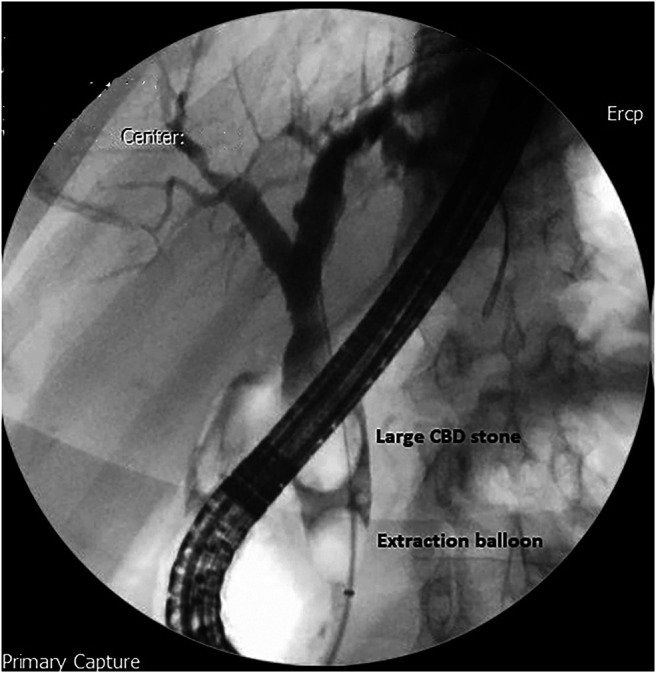

A 65-year-old man presented with several weeks’ history of intermittent jaundice with clay-colored stools, pruritus, and low-grade fever. He also reported a 6 kg weight loss during this period. His ultrasound scan revealed a contracted gallbladder with mild-to-moderate intrahepatic biliary dilatation and dilatated CBD measuring 24 mm with a large distally impacted CBD stone. Subsequently, an ERCP was performed, and a cholangiogram showed a large distal CBD stone of 20 mm with smooth tapering of distal CBD (Figure 1). Sphincterotomy was performed, and mechanical lithotripsy was attempted for stone extraction.